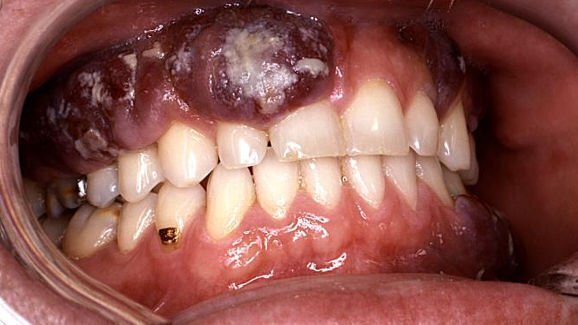

Les résultats peuvent avoir des implications importantes pour les patients VIH-positifs et le sida en particulier, car environ 20 pour cent des patients atteints du VIH développent le sarcome de Kaposi (SK), lésion de la cavité buccale qui peut se développer en tumeurs malignes.

Bien que l'on ne sache pas quel rôle joue le microenvironnement oral dans le développement tumoral du SK, l'étude a démontré que les acides gras à chaîne courte de P. gingivalis et F. nucleatum promeuvent la réplication du virus de l'herpès associé au SK (VHSK), l'agent étiologique associé au SK, a expliqué le chercheur principal, le Dr Fenghun Ye.

Dans l'étude, les chercheurs ont évalué la santé gingivale de 21 patients et étudié leurs échantillons de salive. Onze patients (âge moyen de 50 ans) ont été diagnostiqués avec une maladie chronique grave des gencives et dix participants (âge moyen de 26 ans) avaient des gencives saines. Dans l'ensemble, les chercheurs ont détecté des niveaux significativement plus élevés d'acides gras à chaîne courte dans la salive de patients souffrant de maladies parodontales sévères et ont observé que les acides gras avaient aidé le VHSK à se multiplier. Ils ont également constaté que ce processus avait empêché les molécules du système immunitaire d’arrêter la croissance du virus.